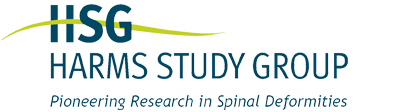

Preop: 1A+ Samples

Preop PA View